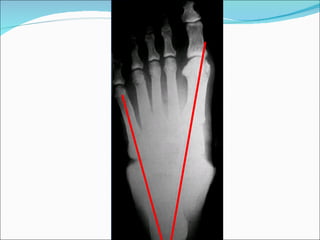

Réalisation technique: Le patient est debout, le pied au milieu du film posé sur le sol.  Le rayon directeur est vertical. Cliché avant-pied en charge. Plan horizontal

Plan horizontal BUTS: Angle d’ouverture du pied entre 1 er  et 5 ème  métatarsien Angle compris entre 1 er  et 2 ème  métatarsien; de métatarsus varus Valgus physiologique du gros orteil Alignement des têtes des métatarsiens

Plan horizontal Étude de l’arche antérieur : étude de l’angle d’ouverture du pied (angle formé par l’axe diaphysaire des premier et cinquième métatarsiens). sa valeur normale est comprise entre 20 et 28°. supérieure à 28°, l’avant-pied est étalé avec affaissement de l’arche antérieur. inférieure à 20°, pied creux antérieur.

Angle de Hallux Valgus:  angle formé par les axes du premier métatarsien et de la première phalange du gros orteil (10°). Plan horizontal